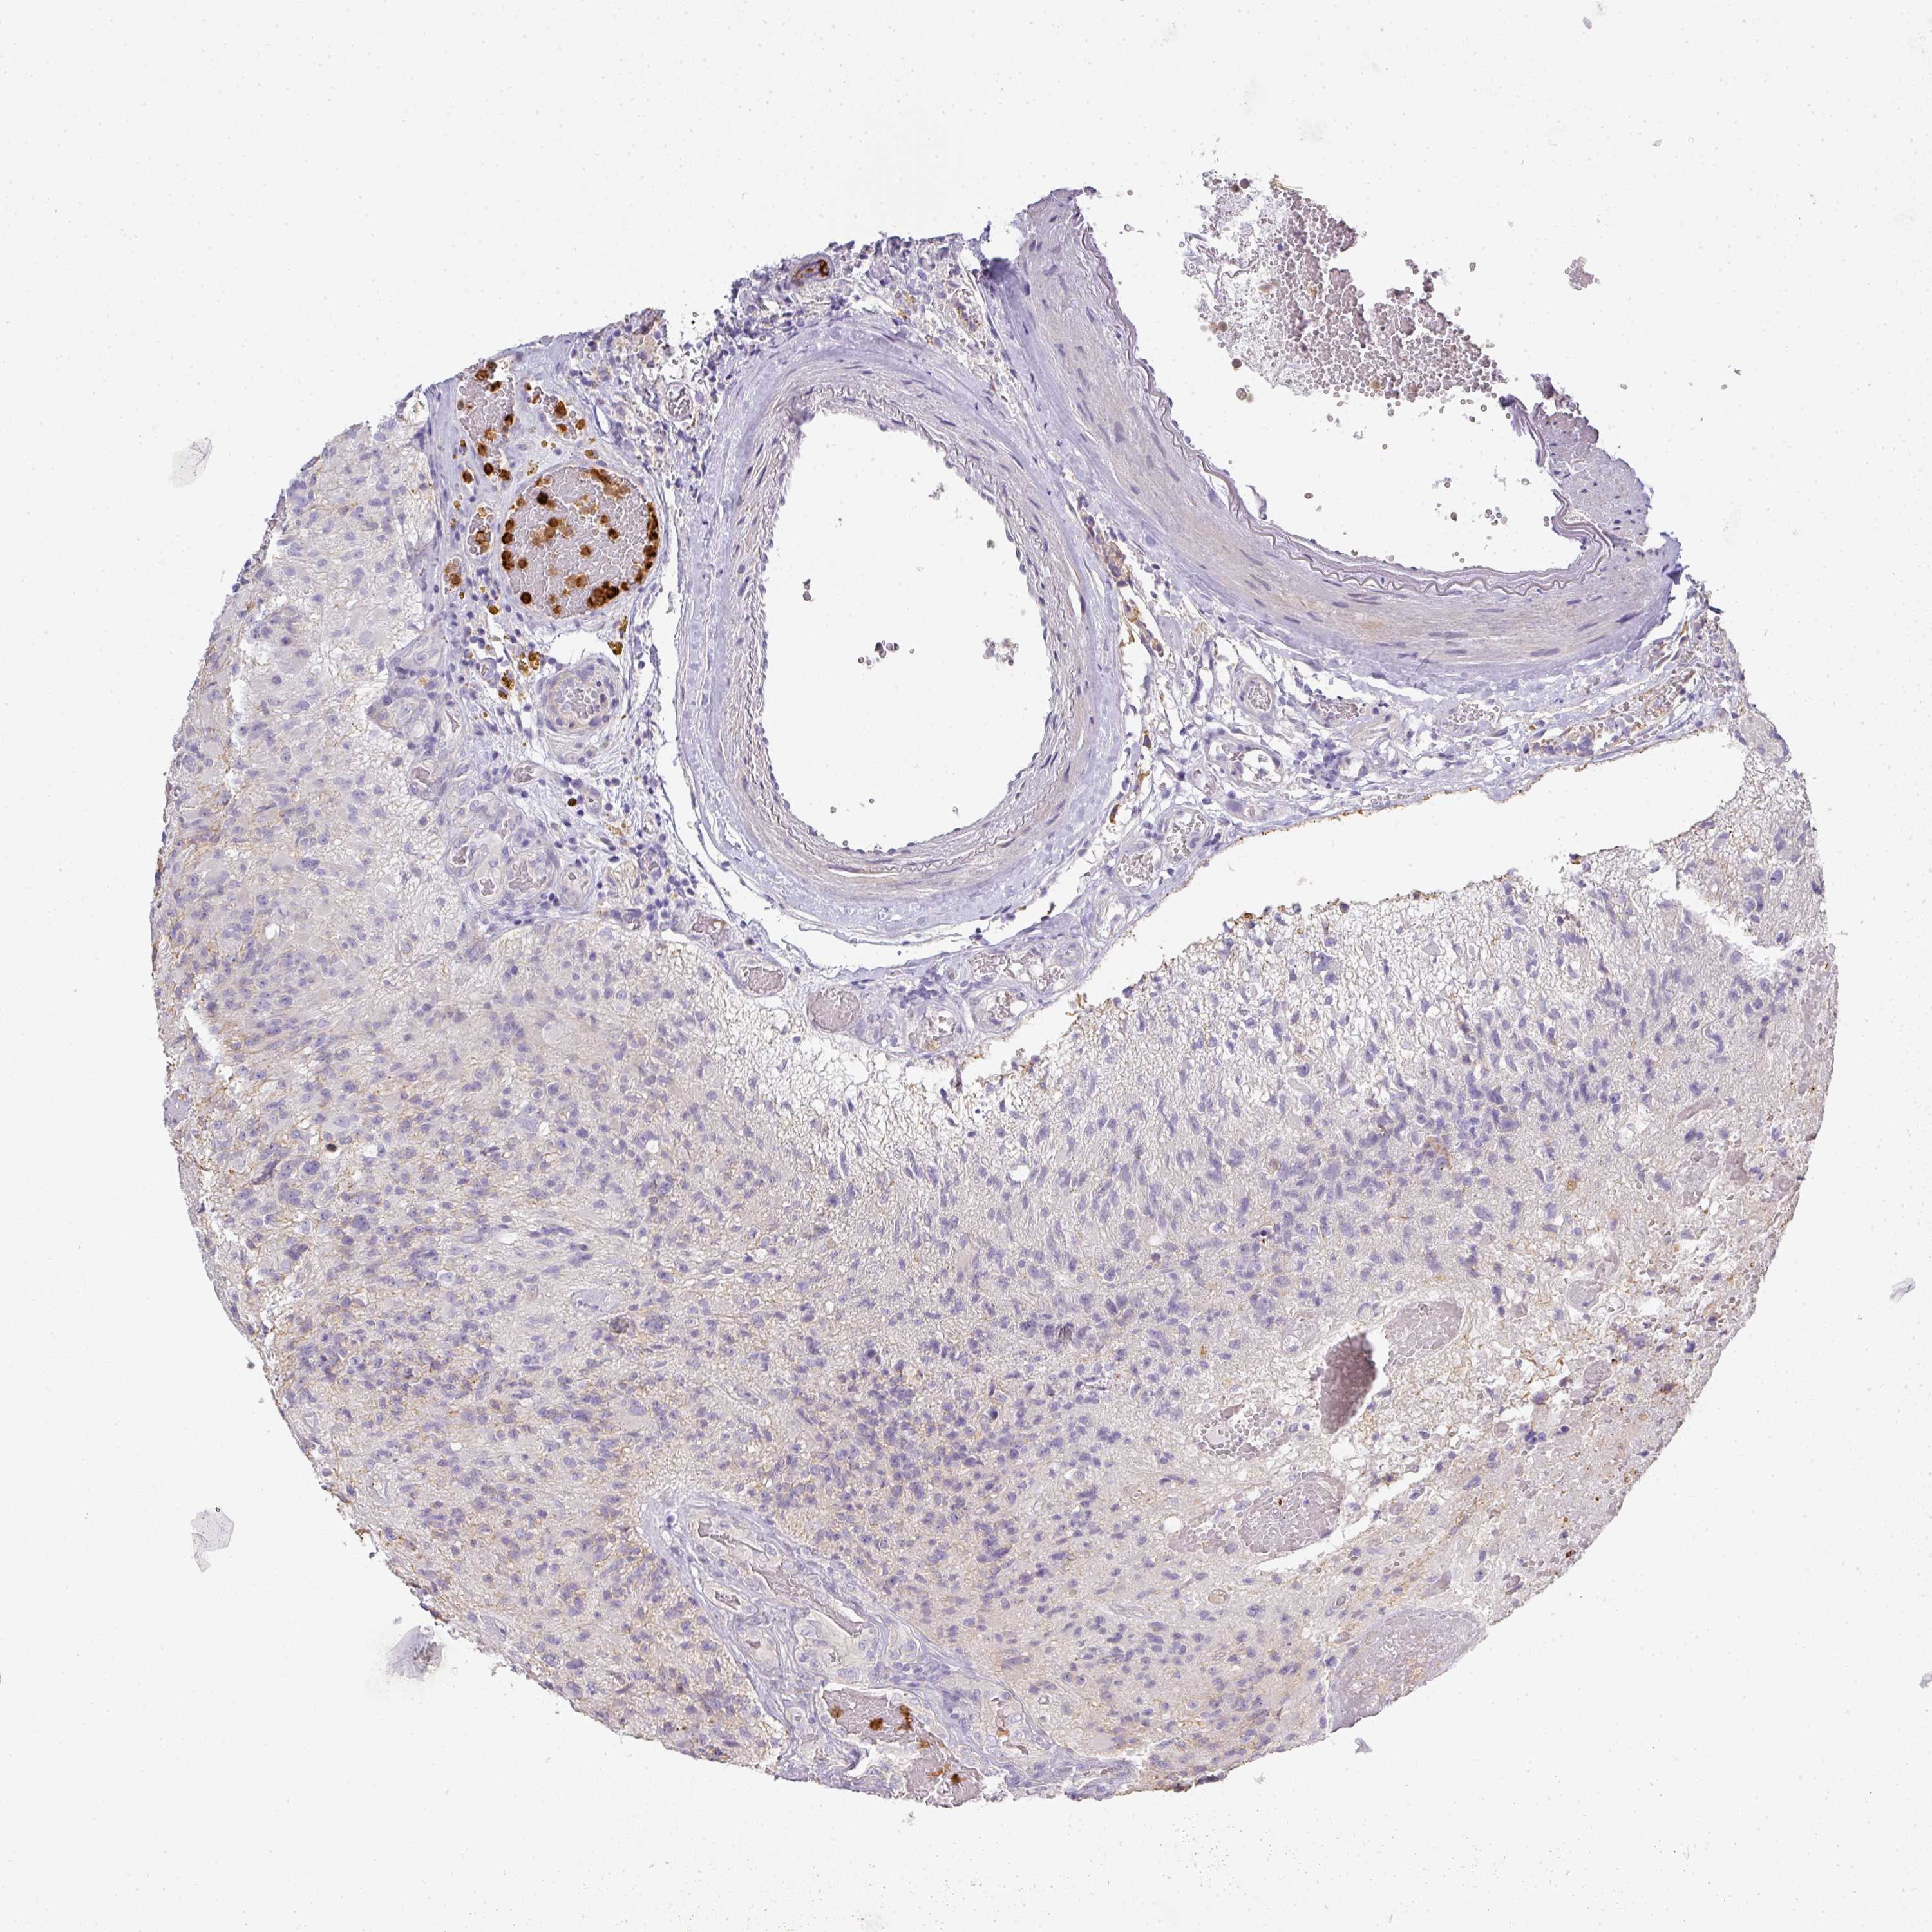

GLIOMA - Protein expressioni

A mouse-over function shows sample information and annotation data. Click on an image to view it in a full screen mode. Samples can be filtered based on level of antibody staining by selecting one or several of the following categories: high, medium, low and not detected. The assay and annotation is described here.

Note that samples used for immunohistochemistry by the Human Protein Atlas do not correspond to samples in the TCGA dataset.

Antibody stainingi

Antibody staining in the annotated cell types in the current human tissue is reported as not detected, low, medium, or high, based on conventional immunohistochemistry profiling in selected tissues. This score is based on the combination of the staining intensity and fraction of stained cells.

Each image is clickable and will lead to virtual microscopy that enables deeper exploration of all samples and also displays staining intensity scores, fraction scores and subcellular localization as well as patient and tissue information for each sample.

Antibody HPA051894

Staining

High

Medium

Low

Not detected

Intensity

Strong

Moderate

Weak

Negative

Quantity

>75%

75%-25%

<25%

None

Location

Nuclear

Cytoplasmic/membranous

Cytoplasmic/membranous,nuclear

Glioma, malignant, High grade

Glioma, malignant, Low grade

Glioblastoma, NOS